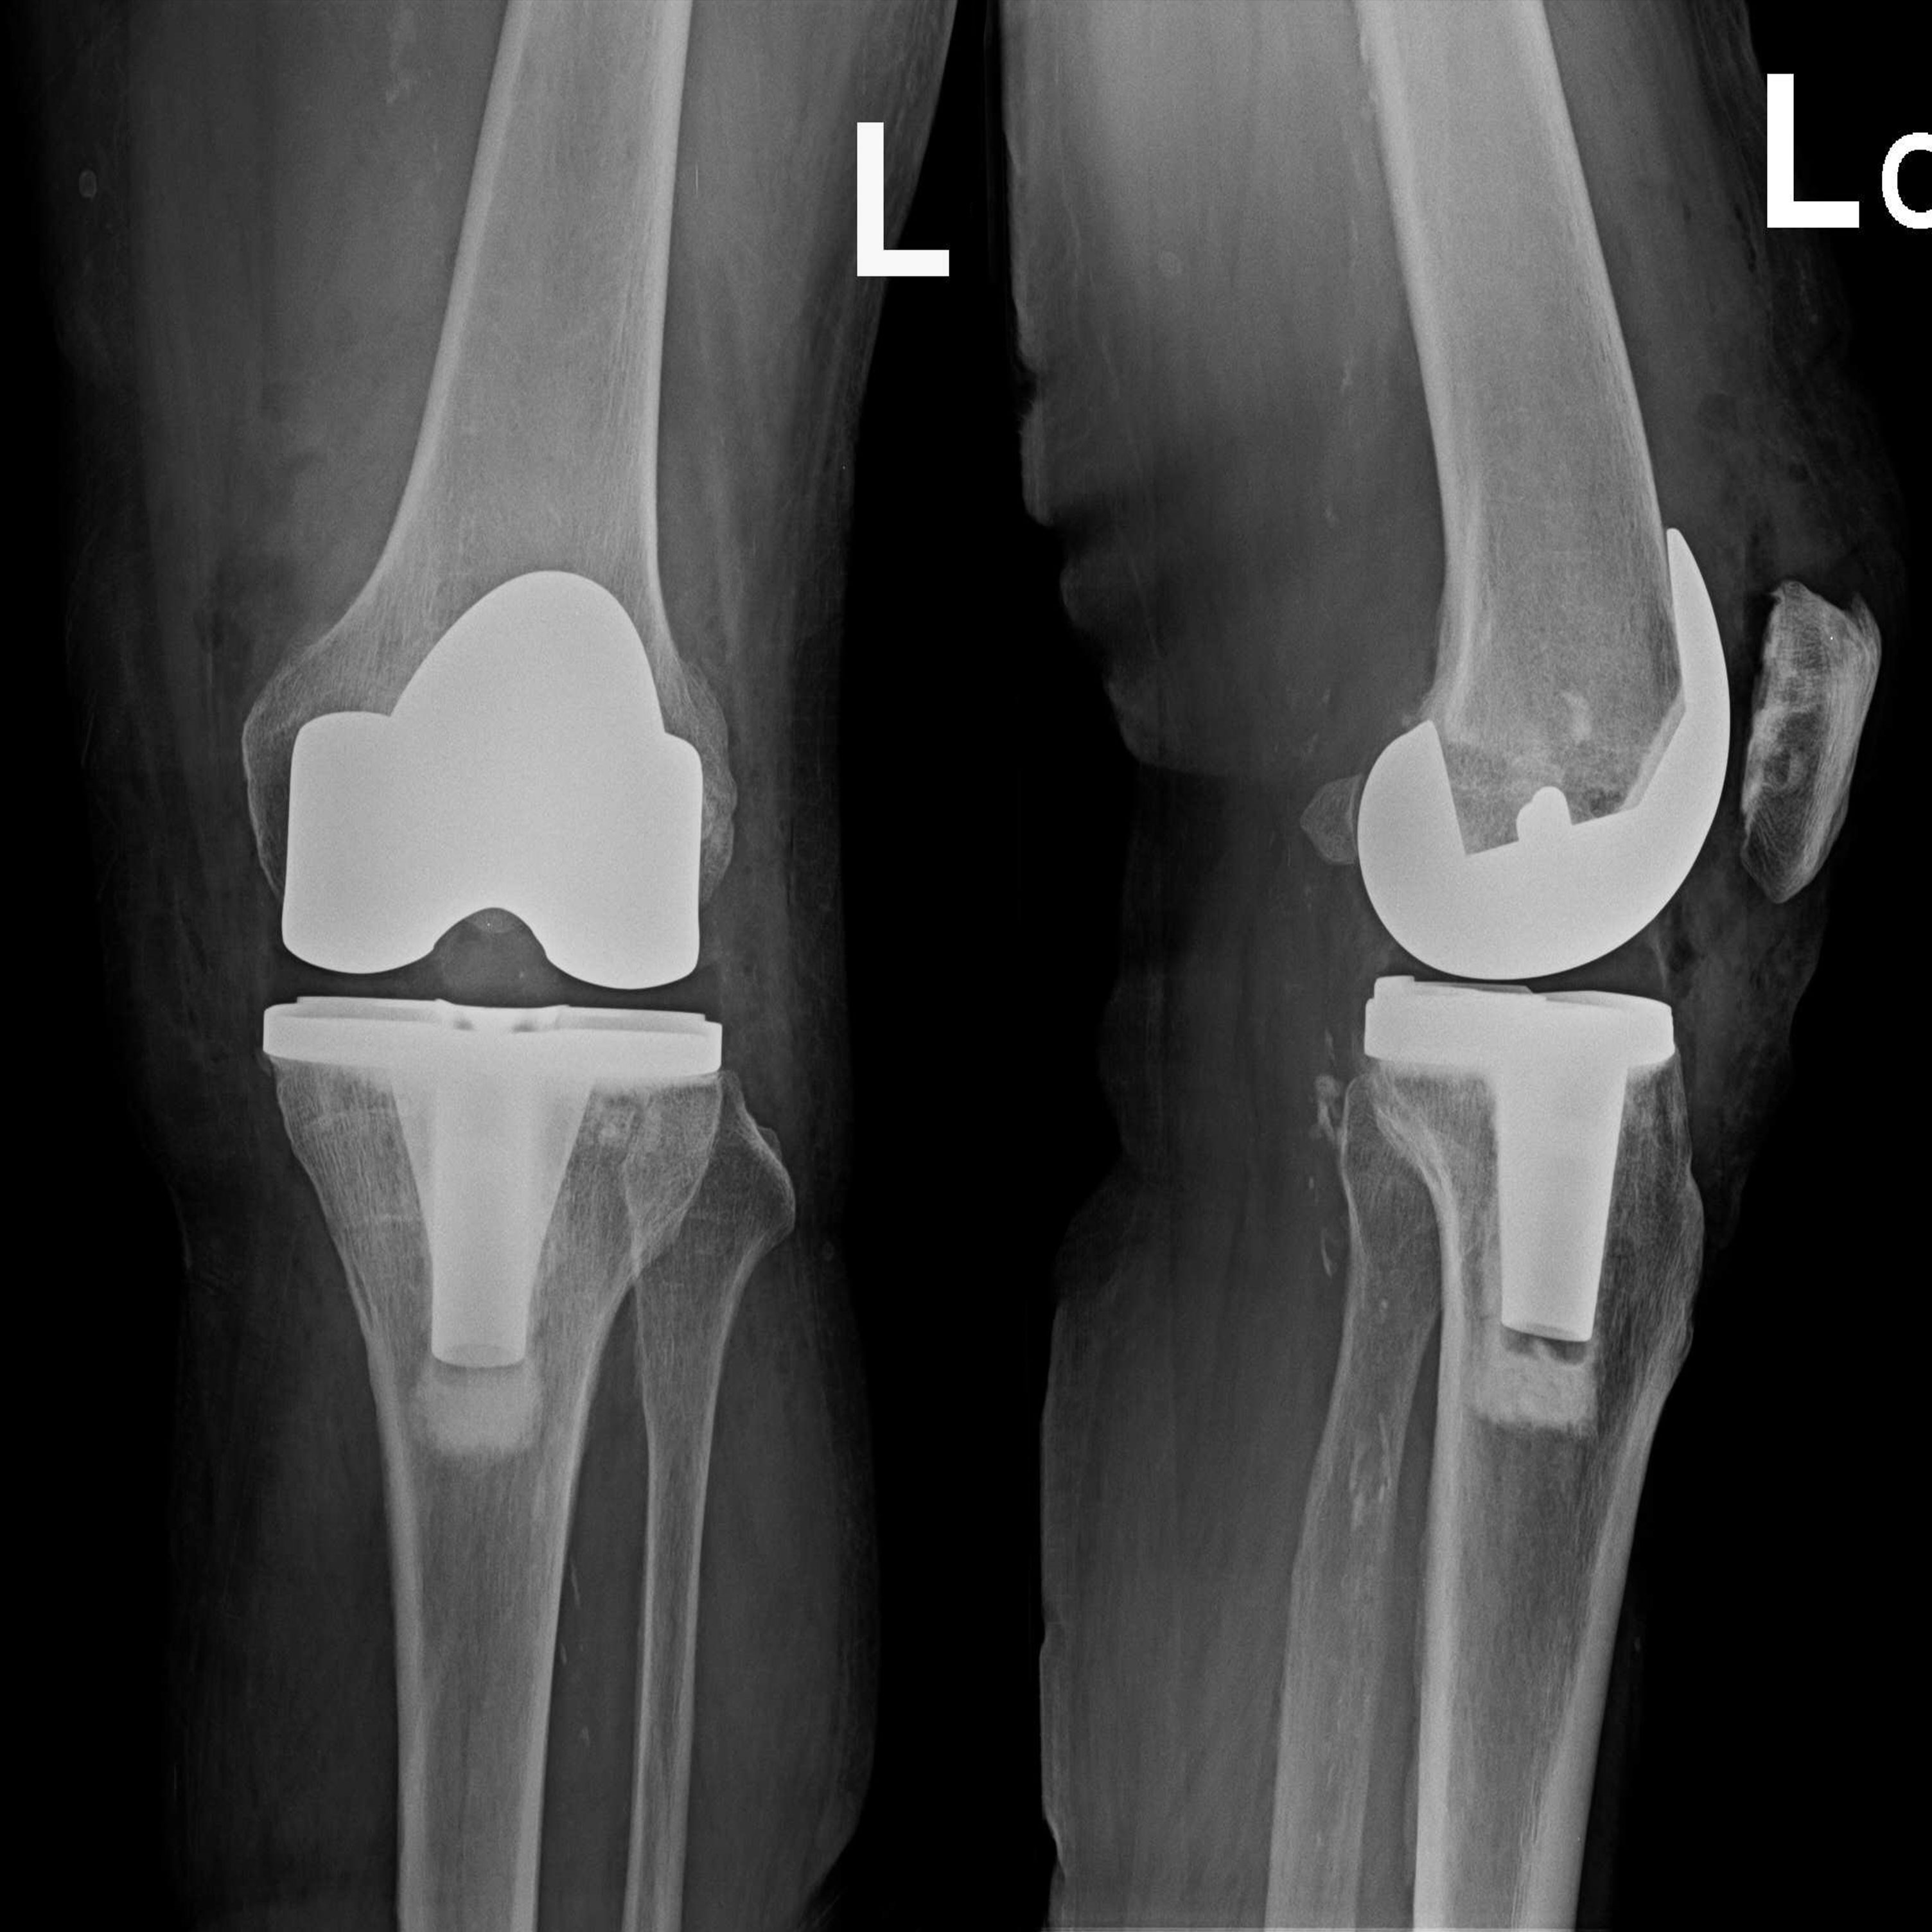

傳統全膝關節置換 首頁 案例分享 膝關節手術 傳統全膝關節置換 江女士 61歲 術前 術後 劉先生 83歲 術前 術後 70歲 柯先生 術前 術後 75歲 黃女士 術前 術後 77歲 羅女士 術前 術後